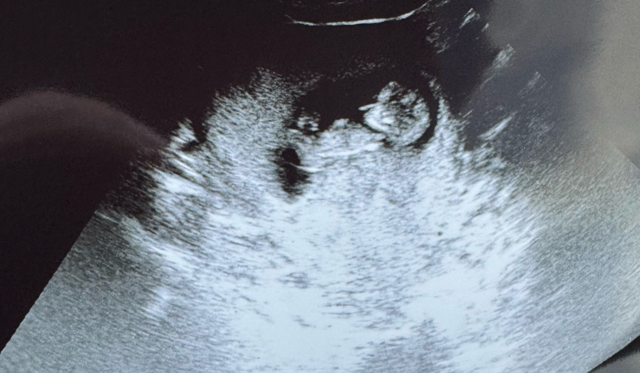

We will be finding out the gender of our 3rd and last baby tomorrow and I am so nervous!! Lol we have 2 little boys now! Any last minute guesses? This ultrasound was at 11 weeks 🤗